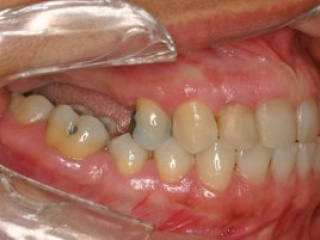

Enxerto de seio maxilar